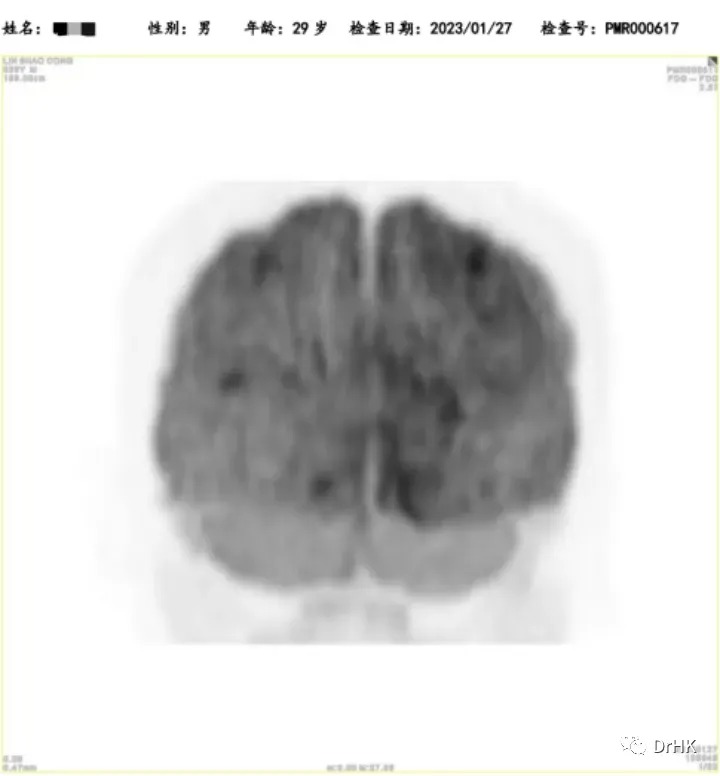

The patient was subsequently followed up regularly, with imaging evaluations completed six months and one year after the transplant. It is gratifying to report that the patient has maintained complete remission throughout this period. The PET images are shown below:

Six-Month Post-Transplant Imaging Evaluation